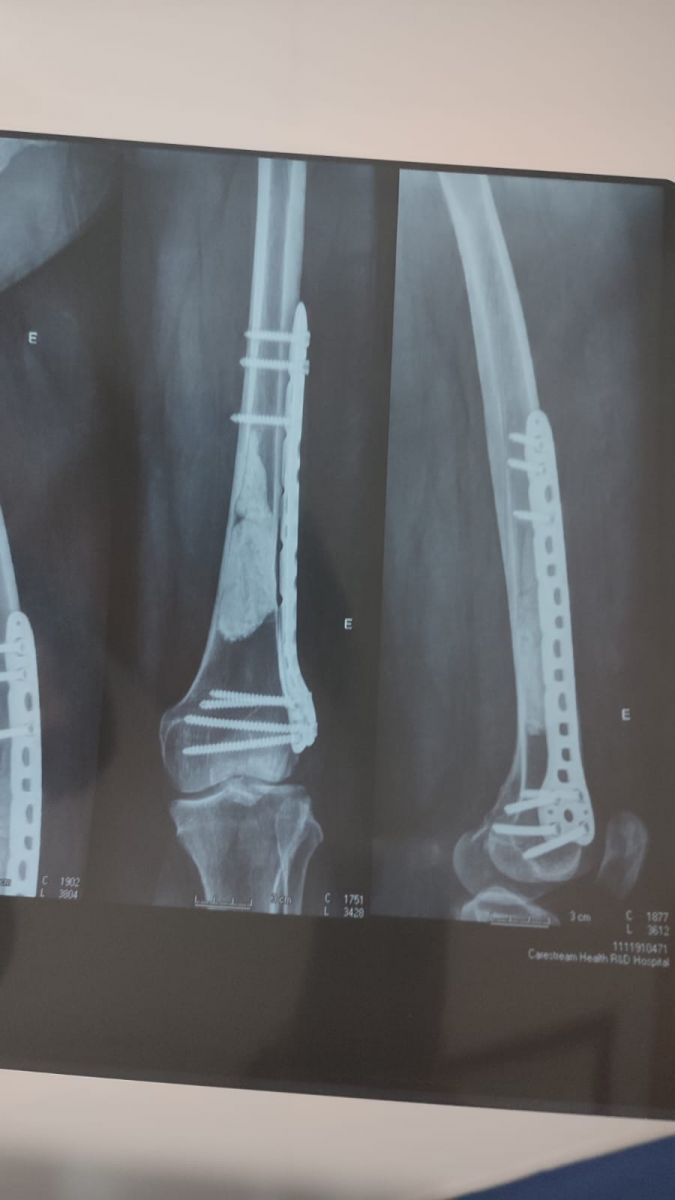

Pinos cirúrgicos no fêmur da jornalista após cirurgia - Foto: acervo de Iule Vargas